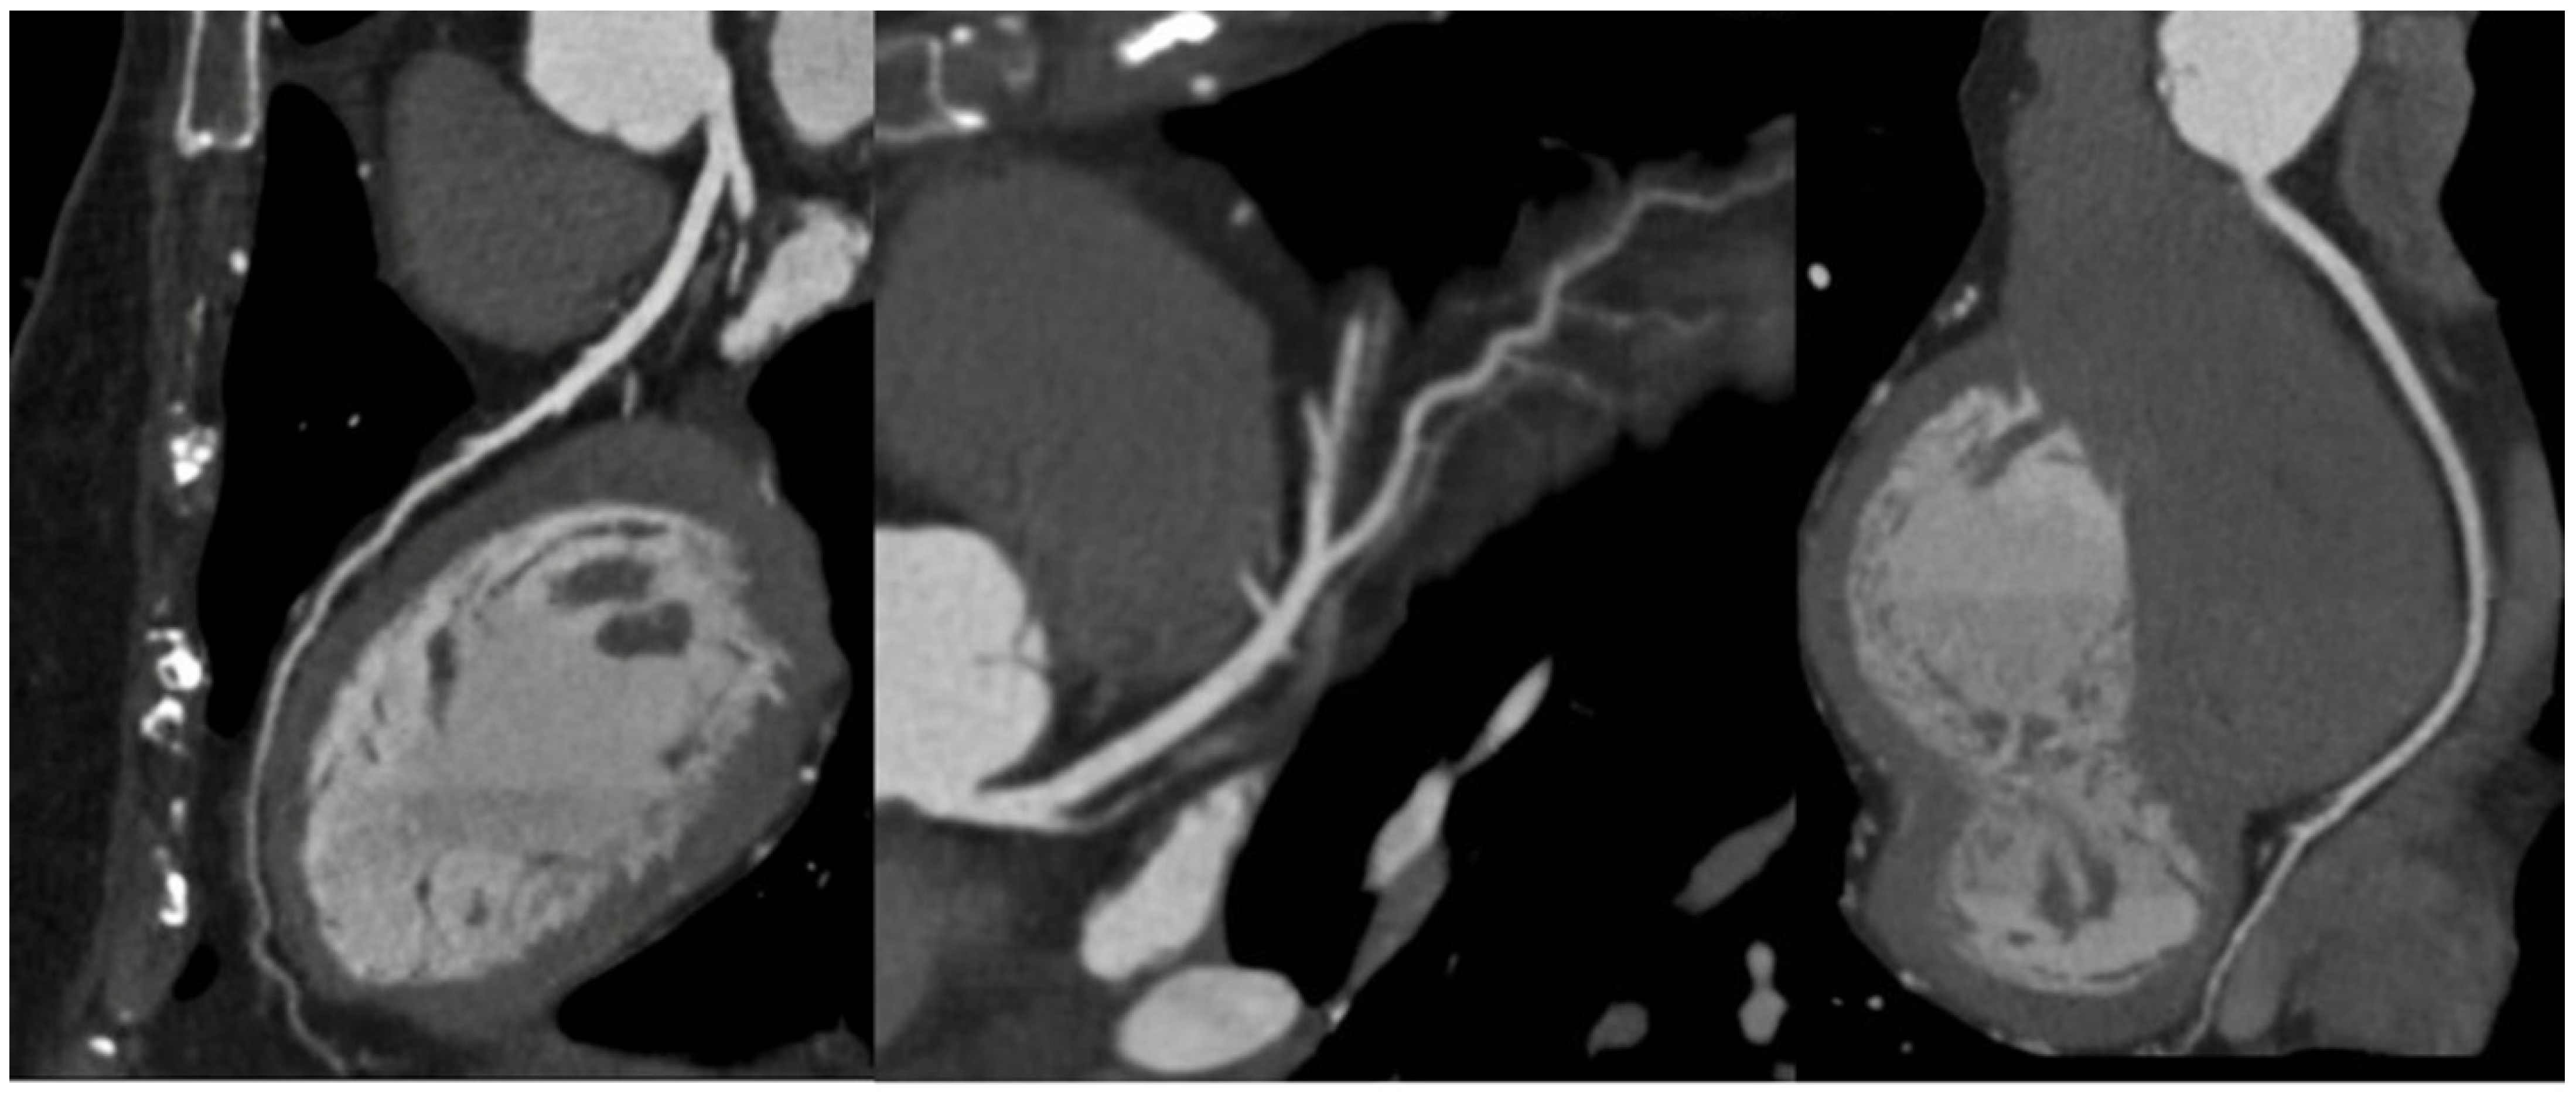

1.1. Computed Tomography

- Cademartiri, F.; Casolo, G.; Clemente, A.; Seitun, S.; Mantini, C.; Bossone, E.; Saba, L.; Sverzellati, N.; Nistri, S.; Punzo, B.; et al. Coronary CT angiography: A guide to examination, interpretation, and clinical indications. Expert Rev. Cardiovasc. Ther. 2021, 19, 413–425. [Google Scholar] [CrossRef]

- Cury, R.C.; Leipsic, J.; Abbara, S.; Achenbach, S.; Berman, D.; Bittencourt, M.; Budoff, M.; Chinnaiyan, K.; Choi, A.D.; Ghoshhajra, B.; et al. CAD-RADSTM 2.0—2022 Coronary Artery Disease-Reporting and Data System. J. Cardiovasc. Comput. Tomogr. 2022, 16, 536–557. [Google Scholar] [CrossRef]

- Ferencik, M.; Mayrhofer, T.; Bittner, D.O.; Emami, H.; Puchner, S.B.; Lu, M.T.; Meyersohn, N.M.; Ivanov, A.V.; Adami, E.C.; Patel, M.R.; et al. Use of High-Risk Coronary Atherosclerotic Plaque Detection for Risk Stratification of Patients With Stable Chest Pain. JAMA Cardiol. 2018, 3, 144. [Google Scholar] [CrossRef]

- Oikonomou, E.K.; Marwan, M.; Desai, M.Y.; Mancio, J.; Alashi, A.; Hutt Centeno, E.; Thomas, S.; Herdman, L.; Kotanidis, C.P.; Thomas, K.E.; et al. Non-invasive detection of coronary inflammation using computed tomography and prediction of residual cardiovascular risk (the CRISP CT study): A post-hoc analysis of prospective outcome data. Lancet 2018, 392, 929–939. [Google Scholar] [CrossRef]